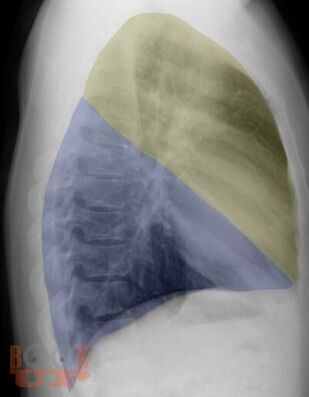

Рентгеноанатомия органов грудной клетки

В учебном пособии представлена информация о нормальной рентгеновской анатомии органов грудной полости, вариантной анатомии, наиболее частых аномалиях развития, скиалогии, алгоритме описания рентгенограмм и основных требованиях по оформлению протокола рентгенологического исследования.